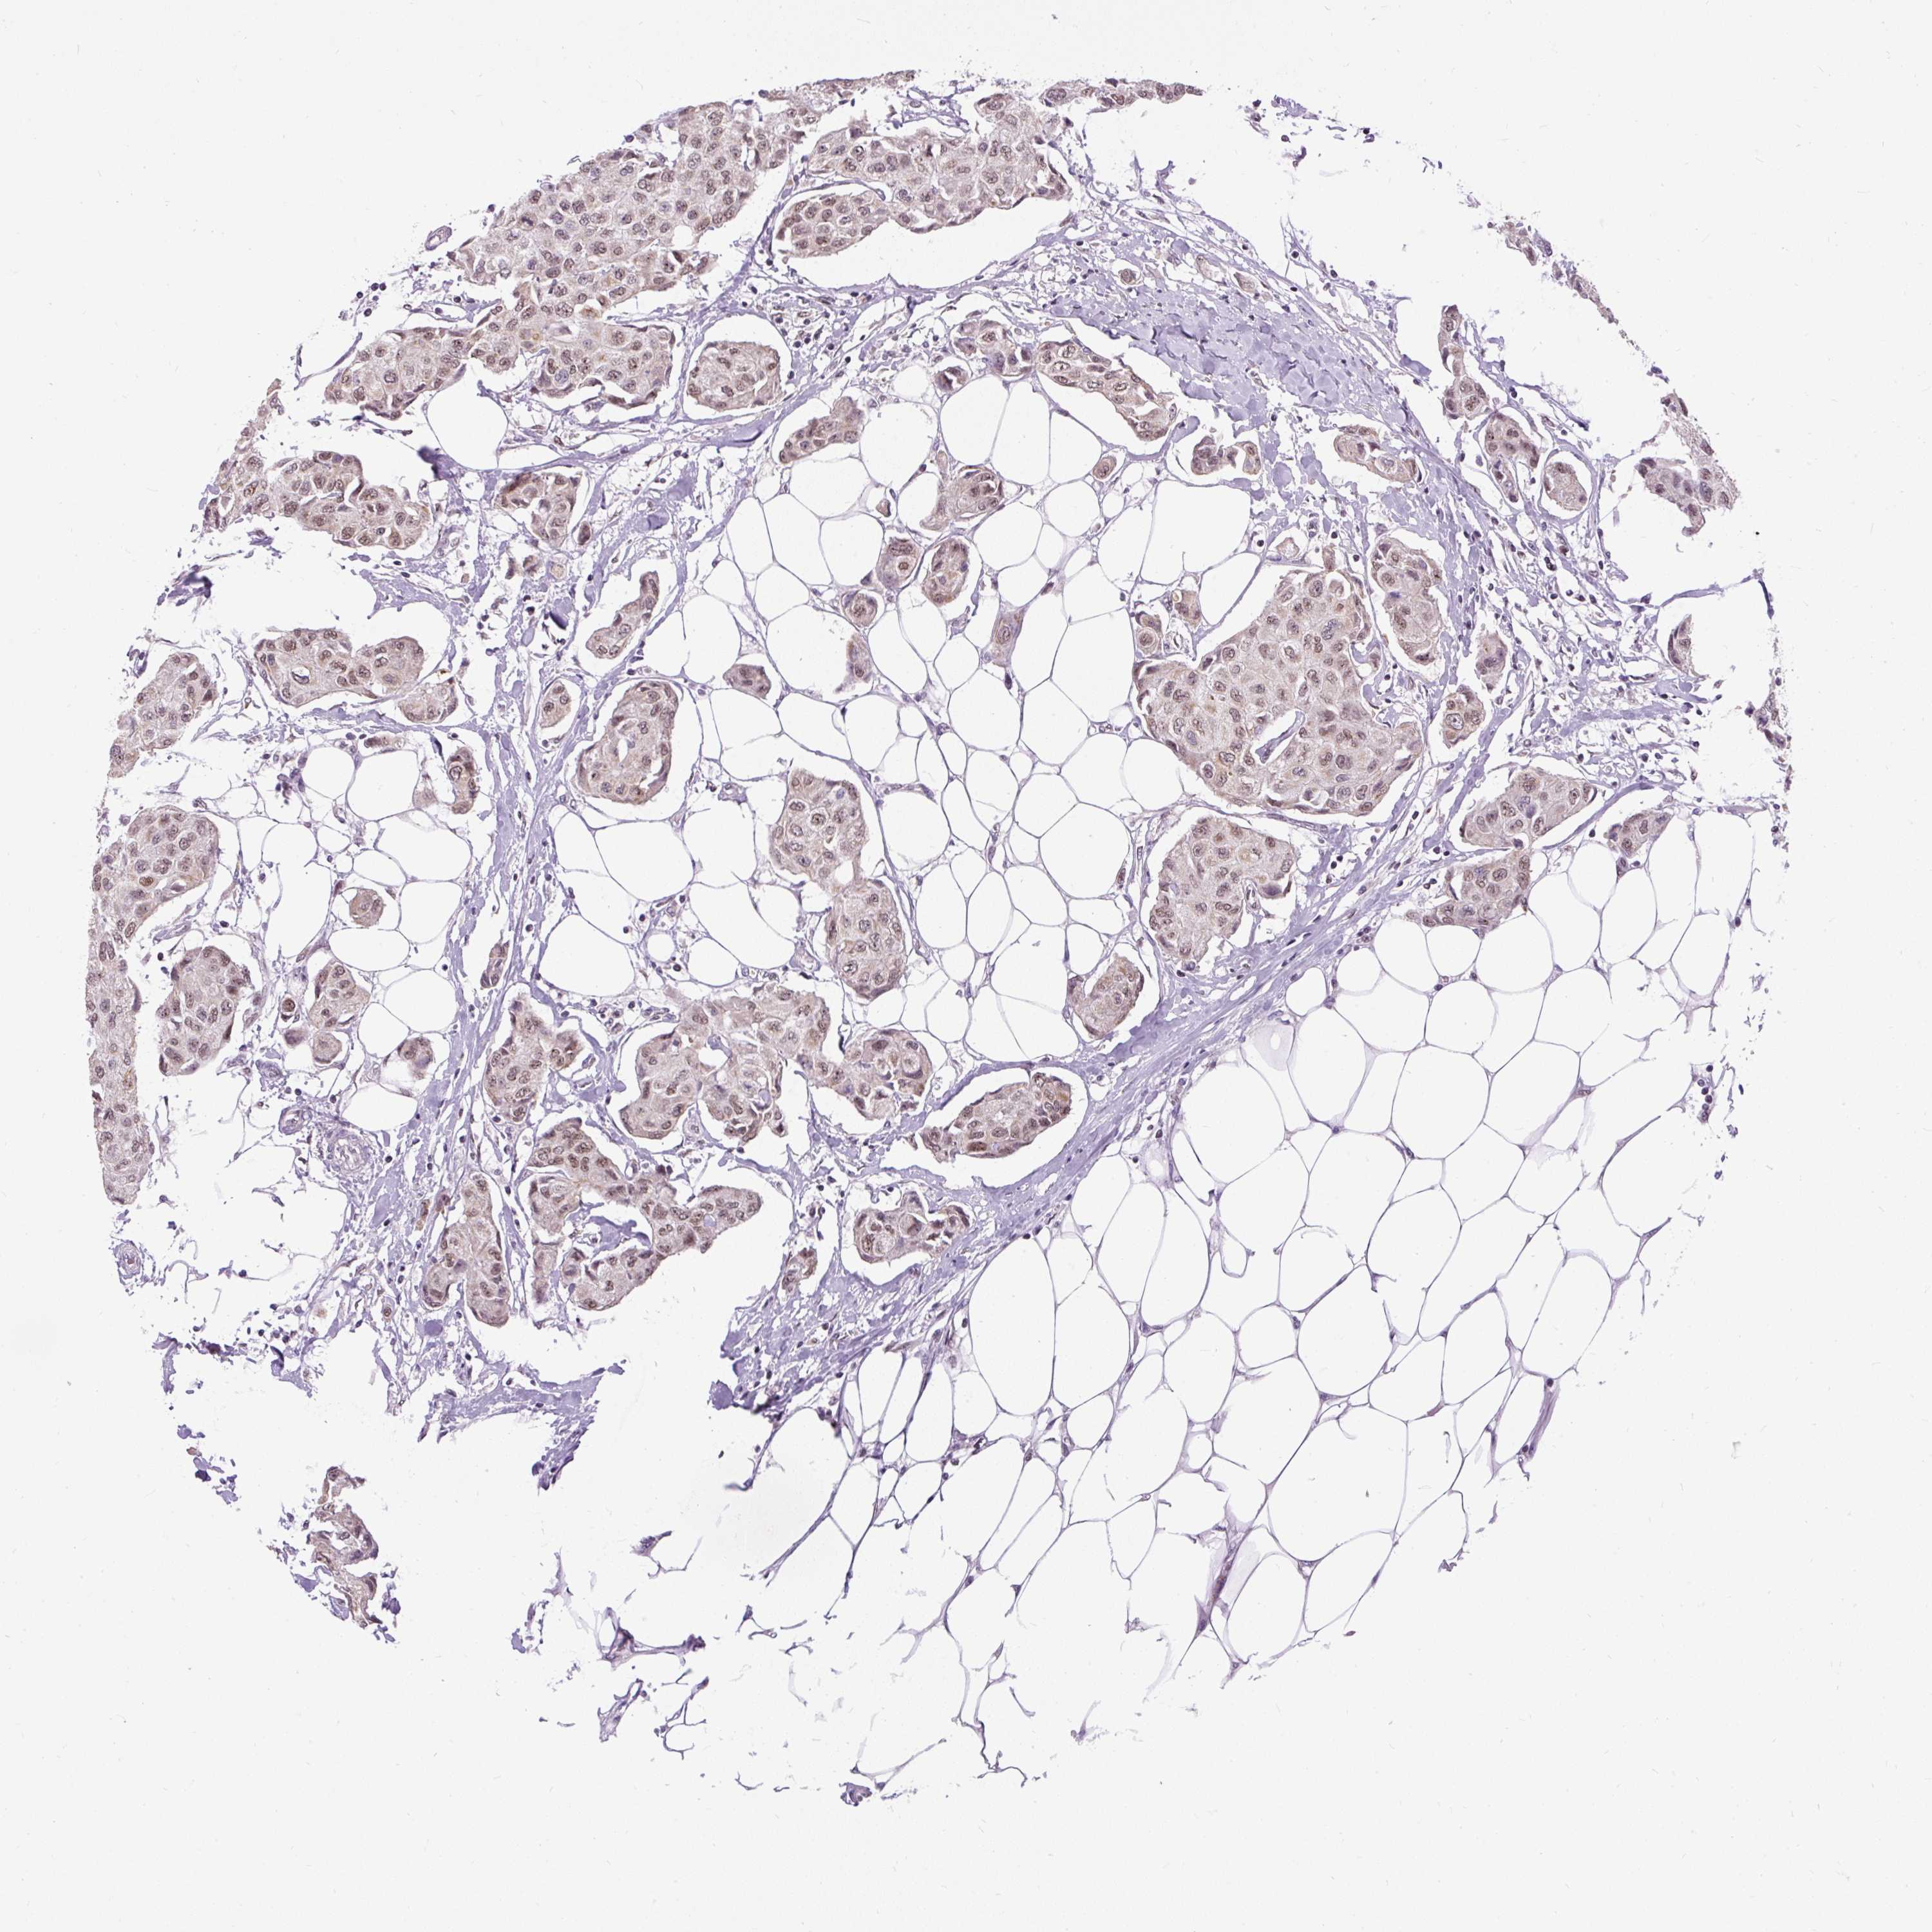

CANCER BREAST CANCER Show tissue menu

BRCA TCGA BRCA VALIDATION PROTEIN EXPRESSION